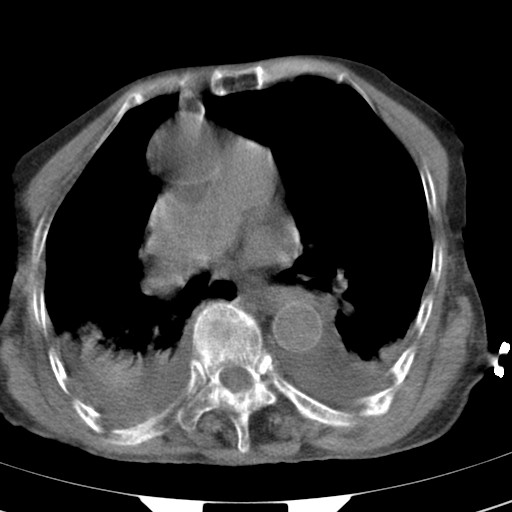

标题: CT21467:女,93岁,摔伤后检查。 [打印本页]

女,93岁,摔伤后检查。

右肺炎症,心功能不全伴双侧胸腔积液,右下肺膨胀不全,食管裂孔疝,冠脉钙化,心包少量积液,左侧肋骨骨折,请上传骨窗.

食管裂孔疝

创伤性湿肺,双侧胸腔积液。可能有食管裂孔疝,进一步检查。骨折有无根据自己的机器及片子再仔细看吧。

右侧锁骨\\肩胛骨骨折、右侧湿肺,心功能不全伴双侧胸腔积液,右下肺膨胀不全,左膈破裂或食管裂孔疝,冠脉钙化,心包少量积液,请上传骨窗.

右肺炎症,心功能不全伴双侧胸腔积液,右下肺膨胀不全,食管裂孔疝,冠脉钙化,心包少量积液,左侧肋骨骨折,右肩甲骨粉碎性骨折。93岁,高寿哇!